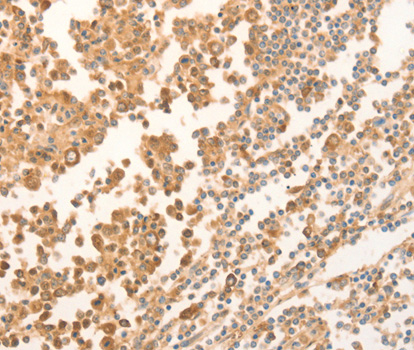

Immunohistochemistry of paraffin-embedded human tonsil tissue using NAP1L1 antibody.

• A2769: image 3

Immunohistochemistry of paraffin-embedded rat pancreas using NAP1L1 antibody at dilution of 1:200 (400x lens).